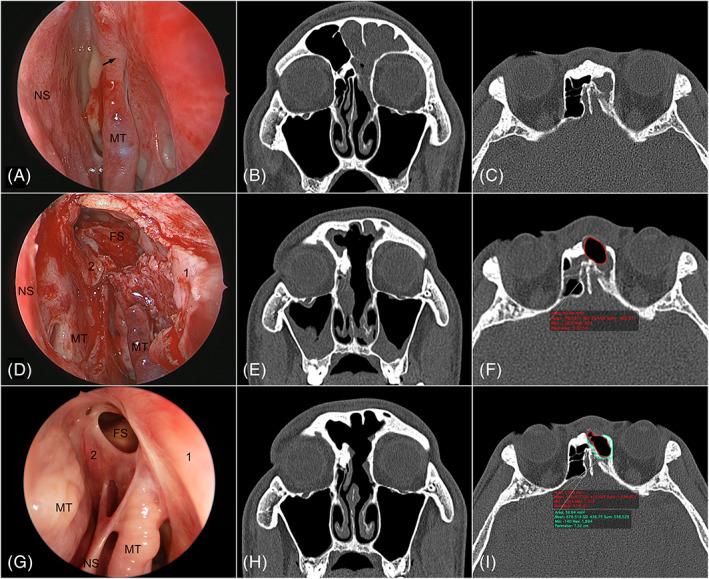

Although several mucosal flap techniques have been reported to improve the outcomes in Draf IIb and Draf III procedures, there is scant knowledge on frontal ostium neo-osteogenesis after reconstruction with mucosa flap. This study evaluates the potential benefits of mucosa flaps on frontal ostium neo-osteogenesis after frontal sinus drill-out procedures.

Forty-three patients who underwent extended Draf IIb and Draf III were enrolled. Among them, 20 patients had frontal neo-ostium (FNO) reconstructed by mucosal flap (group A), and 23 patients did not have neo-ostium reconstruction (group B). The cross-sectional area of FNO, frontonasal bone, and the amount of frontal neo-osteogenesis (FNOG) were measured with OsiriX®. In addition, the Global Osteitis Scoring Scale (GOSS), Lund-Mackay score (LMS), and Lund-Kennedy score (LKS) were also evaluated.

At one year postoperatively, the remaining neo-ostium area was significantly larger in group A ( = .001), and group A had significantly less FNOG ( < .05). The month 12 postoperative GOSS score was significantly decreased in group A. In contrast, it slightly increased in group B. Both the average LKS and LMS were significantly reduced in groups A and B at month 12 postoperatively. Still, the average LKS of group A significantly decreased than that of group B at month 12 postoperatively.

Coverage of the bare frontal bone with the mucosal flap could prevent excessive neo-osteogenesis and keep the neo-ostium open widely.